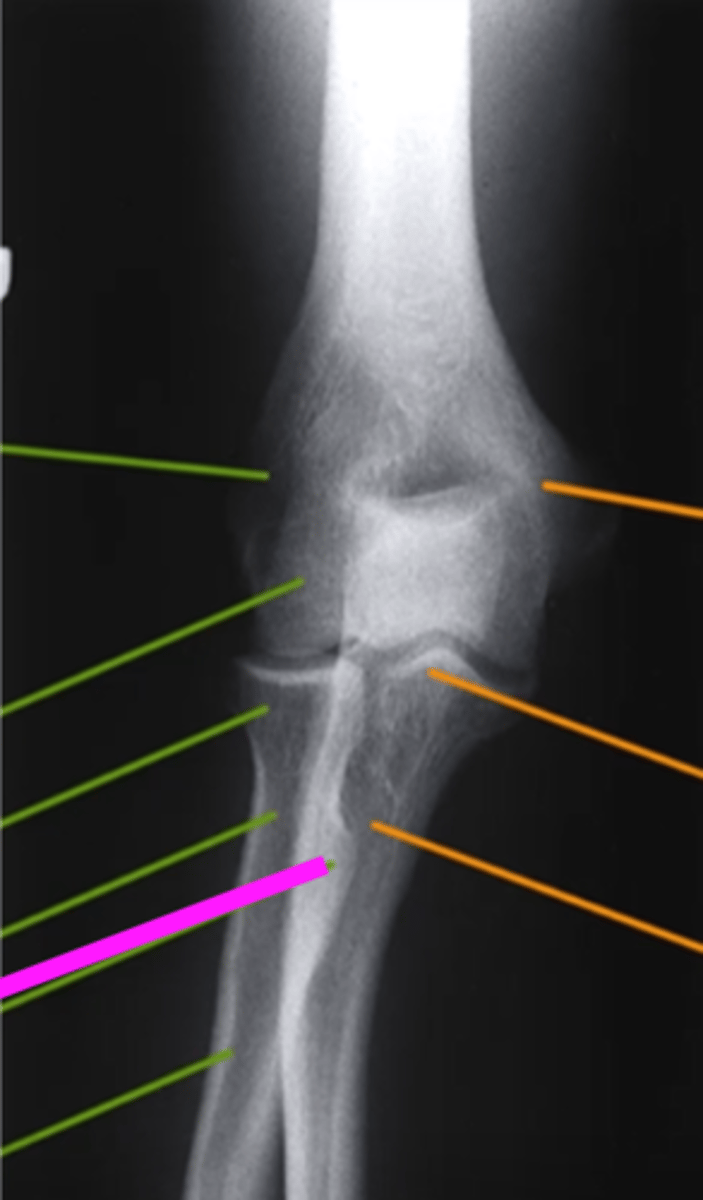

AP Elbow

what view is this

lateral epicondyle

what does the pink line point to?

medial epicondyle

Capitulum

coronoid process

shaft of ulna

shaft of the radius

radial tuberosity

radial head

radial neck